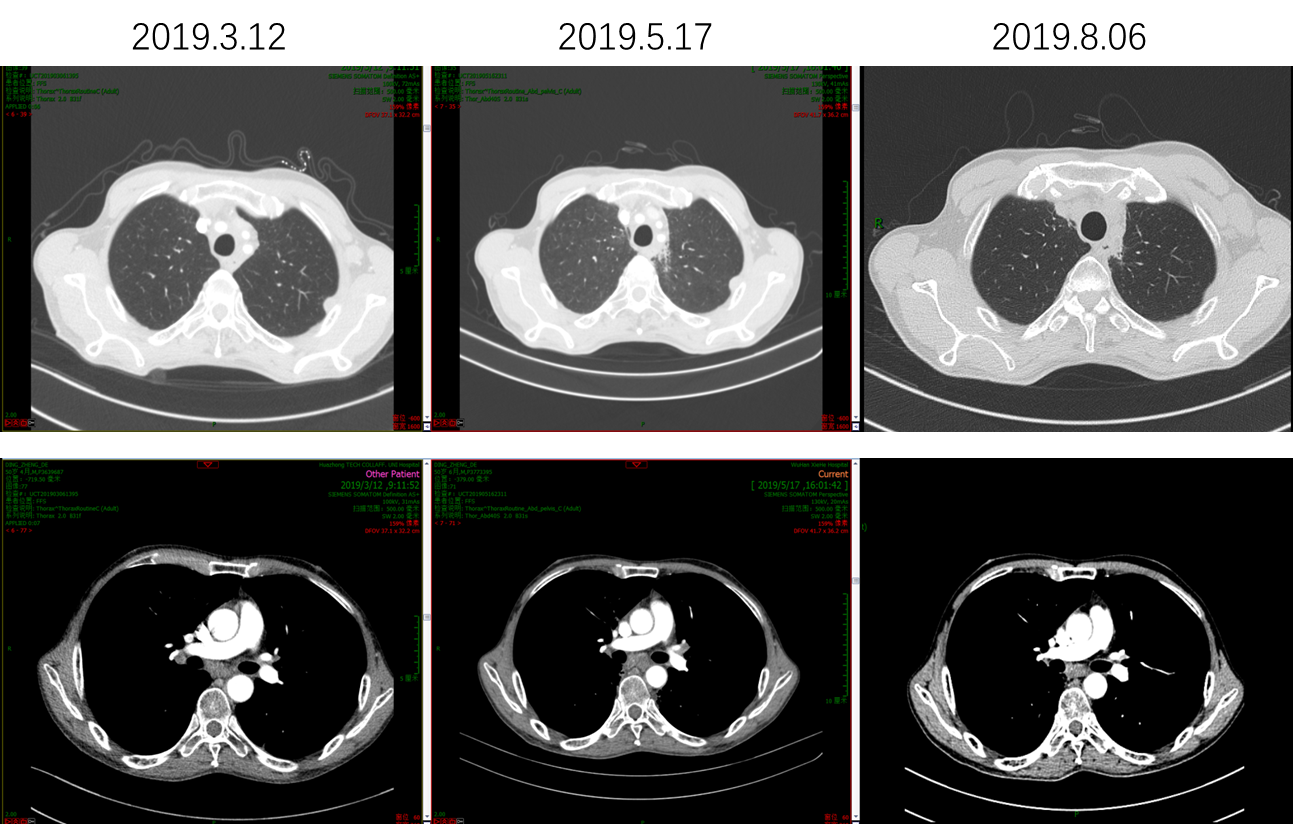

因患者PS评分差,故推荐单药PD-1单抗治疗,患者考虑后选择信迪利单抗。2019年3月20日开始使用信迪利单抗治疗1次,当日出现发热39.3℃,予以退热栓退热治疗后好转。4天后,患者PS评分明显好转,下床活动自如,食欲增强,PS评分由3分改善到1分。2019年4月11日和2019年5月1日分别再使用信迪利单抗治疗各1次。2019年5月17日复查腹部CT,肝脏病灶较前明显缩小,肝门淋巴结较前明显缩小;复查胸部CT,肺部病灶也较前明显缩小。总体疗效评价为PR。多次治疗中外周血EBV-DNA拷贝数检测结果显示,信迪利单抗治疗后EBV-DNA明显降低。

image021.png

图6  信迪利单抗治疗前后肺部病灶明显缩小

分别于2019年5月22日、2019年6月12日、2019年8月13日和2019年9月3日继续使用PD-1单抗治疗4次。治疗后复查,肝脏病灶和肝门淋巴结较前继续缩小,肺部结节较前也明显缩小。患者目前一般情况良好,体重较前有所增加,查血血常规、肝肾功能电解质,甲状腺功能,心肌酶等均正常范围,无发热、皮疹等不良反应。

图10  信迪利单抗继续应用,肺部病灶继续缩小